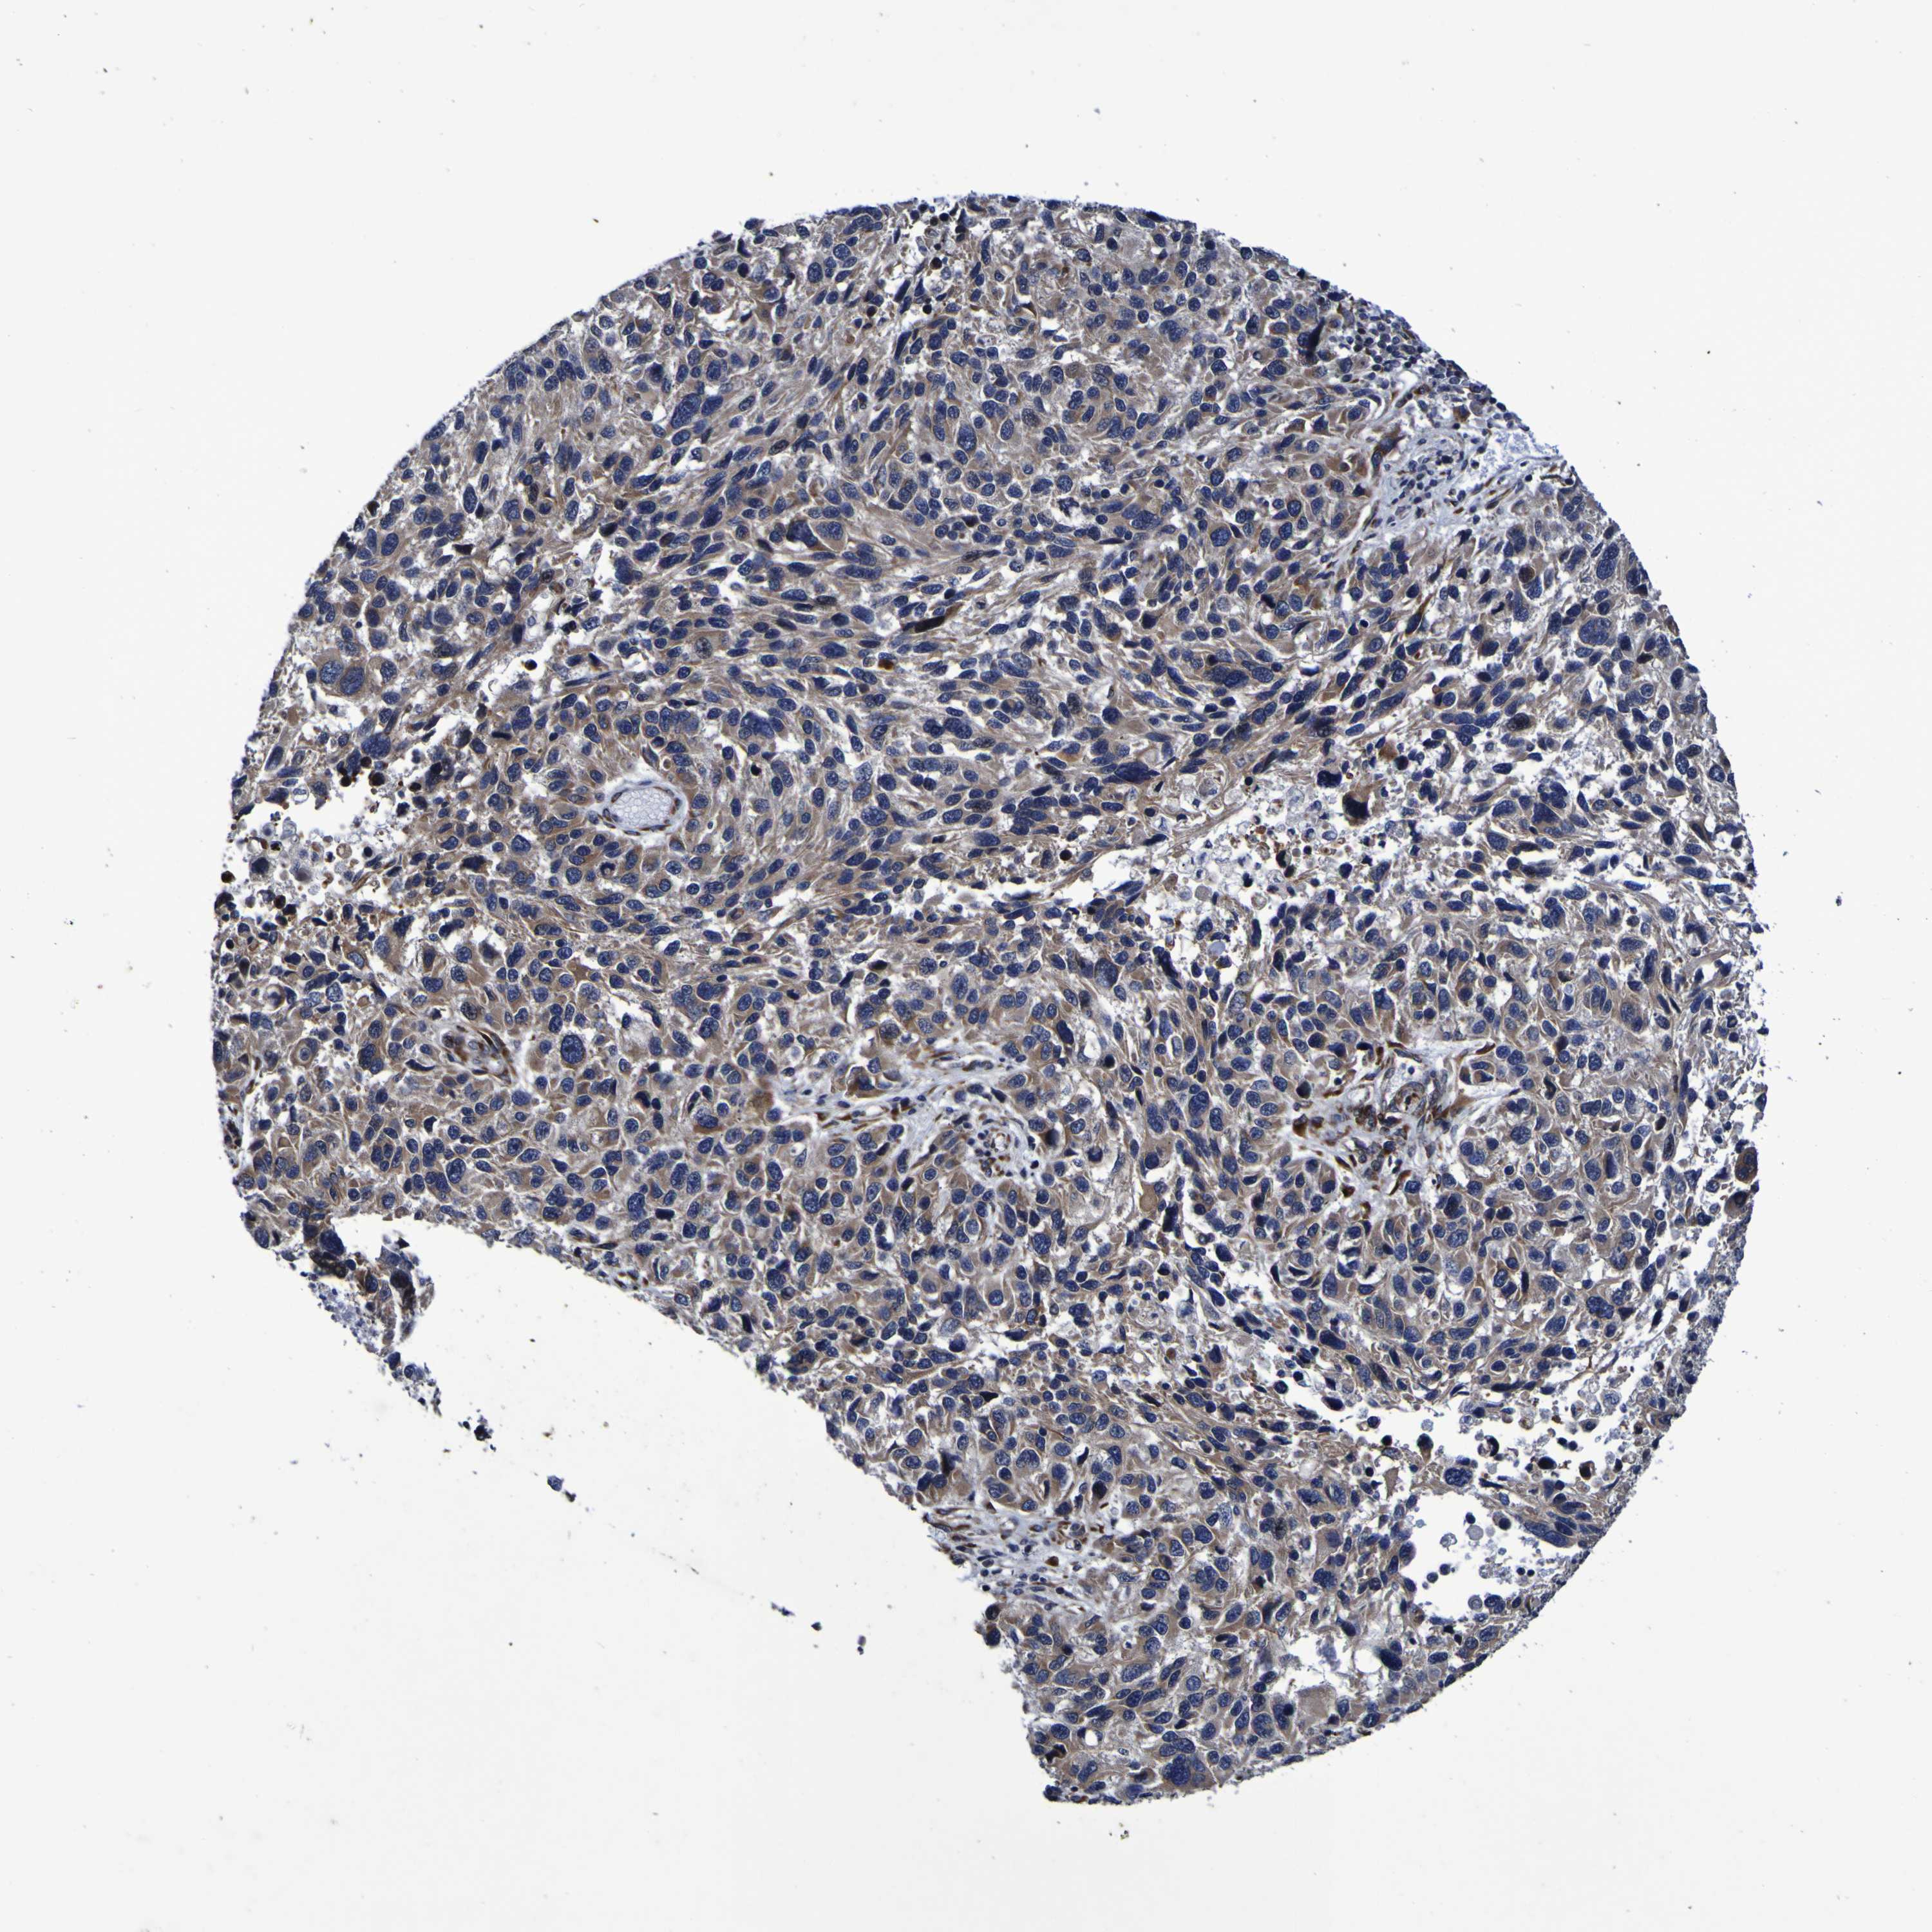

MELANOMA - Protein expressioni

A mouse-over function shows sample information and annotation data. Click on an image to view it in a full screen mode. Samples can be filtered based on level of antibody staining by selecting one or several of the following categories: high, medium, low and not detected. The assay and annotation is described here.

Note that samples used for immunohistochemistry by the Human Protein Atlas do not correspond to samples in the TCGA dataset.

Antibody stainingi

Antibody staining in the annotated cell types in the current human tissue is reported as not detected, low, medium, or high, based on conventional immunohistochemistry profiling in selected tissues. This score is based on the combination of the staining intensity and fraction of stained cells.

Each image is clickable and will lead to virtual microscopy that enables deeper exploration of all samples and also displays staining intensity scores, fraction scores and subcellular localization as well as patient and tissue information for each sample.

Antibody HPA012113

Antibody HPA016980

Staining

High

Medium

Low

Not detected

Intensity

Strong

Moderate

Weak

Negative

Quantity

>75%

75%-25%

<25%

None

Location

Nuclear

Cytoplasmic/membranous

Cytoplasmic/membranous,nuclear

Malignant melanoma, NOS

Malignant melanoma, Metastatic site